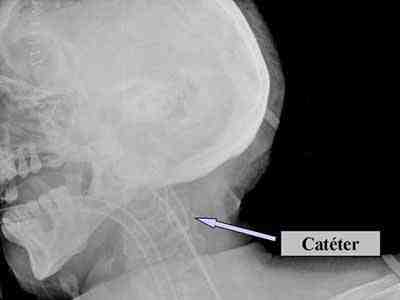

Manejo: Confirmación radiológica

En el caso que presentamos, la presencia del bucle en el catéter, no afectó la posición del extremo del mismo, evidenciado por la radiografía de columna cervical. Los valores de SjO2 superiores a 90% (valores muy “arteriolizados”) observados en Reanimación, se debieron a hiperemia, confirmada con el cálculo de la AVDO2.

Actualmente, la neuromonitorización ha demostrado ser útil y segura, mejorando la morbimortalidad, debido a que se detecta la isquemia cerebral de forma temprana. Sin embargo, uno de los principales problemas y errores durante la monitorización de la SjO2 es que la punta del catéter no esté colocada en el bulbo de la yugular. Este hecho nos puede llevar a falsos diagnósticos y, en consecuencia, a tratamientos erróneos. Por eso creemos muy recomendable no iniciar ningún tratamiento hasta que se haya comprobado con una prueba de imagen que la punta del catéter está correctamente colocada.

Figura 1. Visualización por Radiografía de cráneo del bucle del catéter del golfo de la yugular.